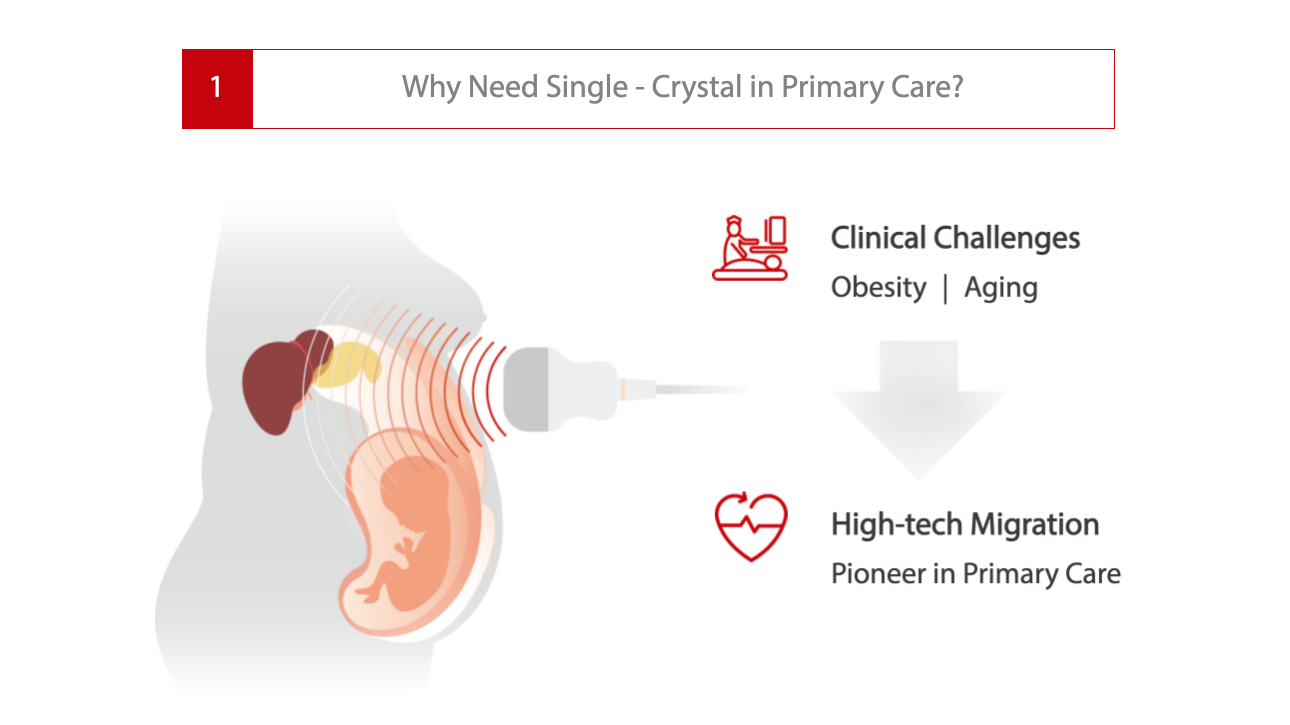

AtenciĂłn primaria con Pure Crystal

AtenciĂłn primaria con Pure Crystal

Nivel de cristal Ășnico